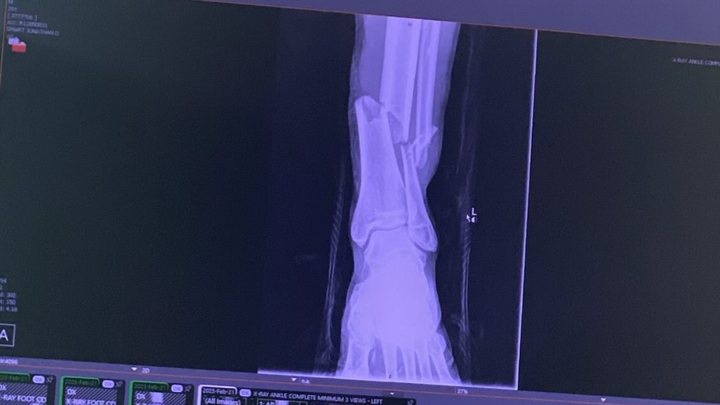

This is a fundraiser to help Michael Deon with his medical bills from our recent fight on Feb 21st. He suffered a complete break of his left leg and he underwent surgery the following day. He now has a Titanium Rod in his shin. We’re wishing him a speed recovery and donations would be greatly appreciated